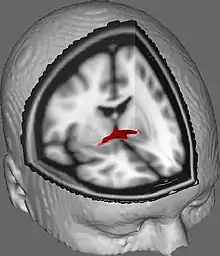

Coronal cross-section of brain showing the anterior commissure. (left, third from bottom.) | |